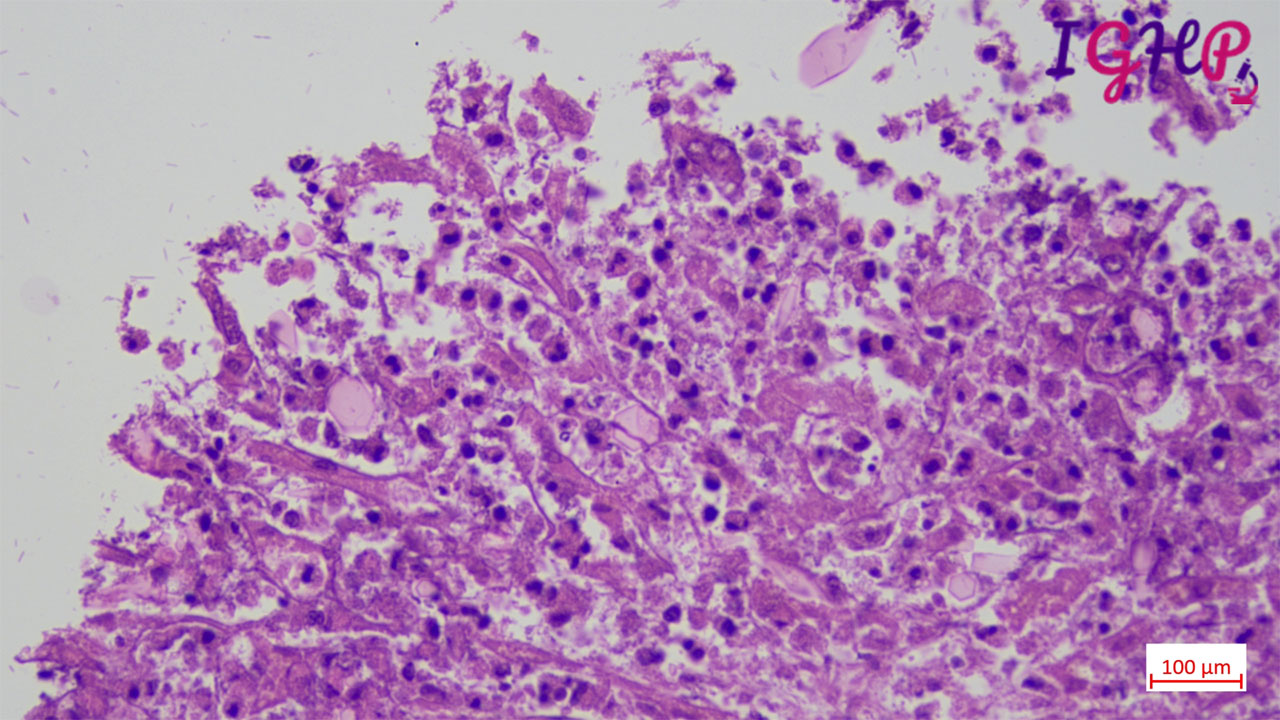

Microscopic Images-

Microscopic examination showed eosinophilic abscess with multiple cholesterol clefts.

PAS, MT and Orcein stains performed showed presence of CharcotLayden crystals.